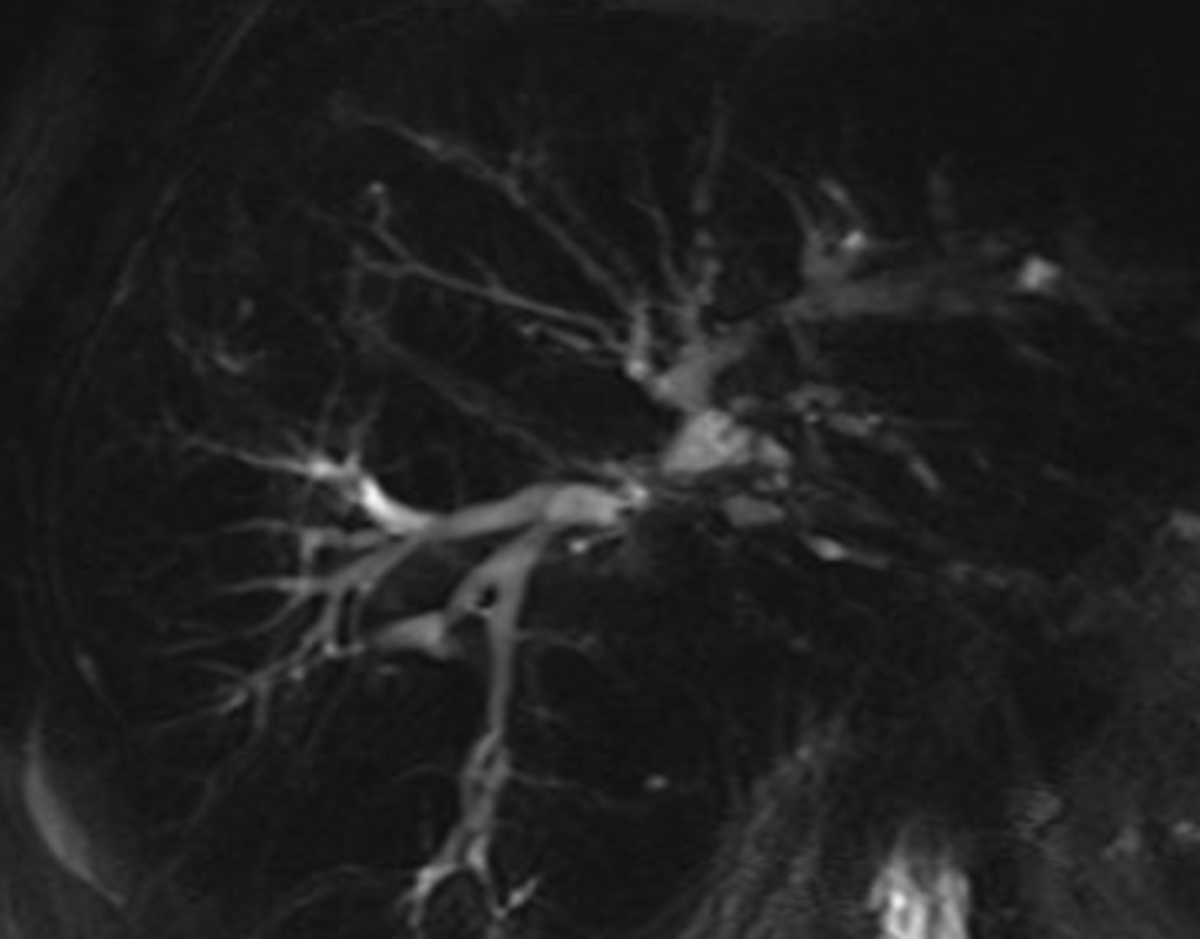

29M inc LFTS, asymptomatic. PE without evidence of jaundice, hepatomegaly or splenomegaly. His laboratory test results are notable for total bilirubin 2.0 mg/dL (normal: 0.3-1.2 mg/dL), AST 51 U/L (normal: 0-35 U/L), ALT 64 U/L (normal: 0-35 U/L), and alkaline phosphatase is 168 U/L (normal: 36-92 U/L). MRCP figure. What is the best next step in his management?

• Primary sclerosing cholangitis (PSC) should be considered in patients with a cholestatic pattern of liver test abnormalities particularly an elevated alkaline phosphatase.

• The diagnosis is then made by cholangiographic evidence of characteristic bile duct changes (multifocal strictures, segmental dilations).

• MRCP for dx

• In patients with characteristic findings on cholangiography, a liver biopsy is typically not required.

• Inflammatory bowel disease (IBD) in patients with PSC may frequently be asymptomatic and have a quiescent course. Therefore, a full colonoscopy with biopsies is recommended in patients with PSC regardless of the presence of symptoms to screen for IBD.